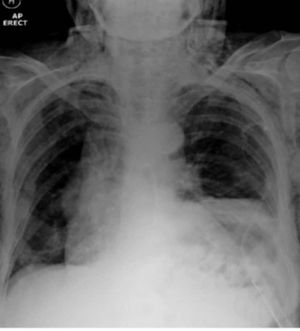

Unilateral left-sided pleural effusions with cardiomegaly may be due to pericardial disease. Im not sure... Therefore when describing pleural effusions please make sure the clinical signs and history match with the xray because pneumonia and pulmonary embolism may also cause pleural effusions in patients with heart failure.